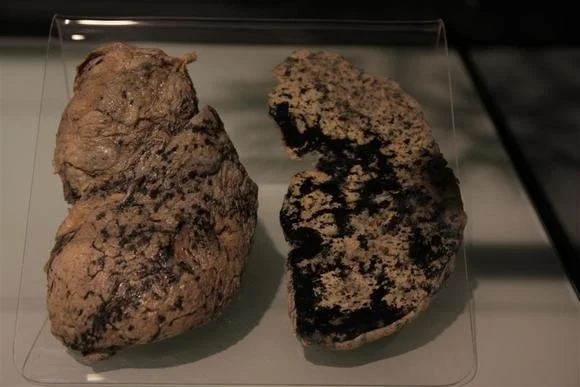

Здоровый образ жизни: Влияние курения